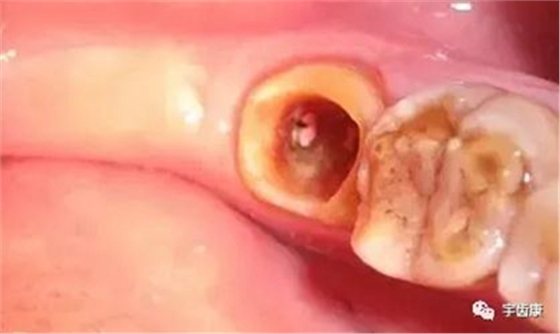

1. 保護牙體組織

防止過度預(yù)備(造成牙髓激惹)

保留活髓(保留牙體的整體性和韌性)

過度預(yù)備抗力形喪失

保留活髓及其整體性

保留較多的牙體組織